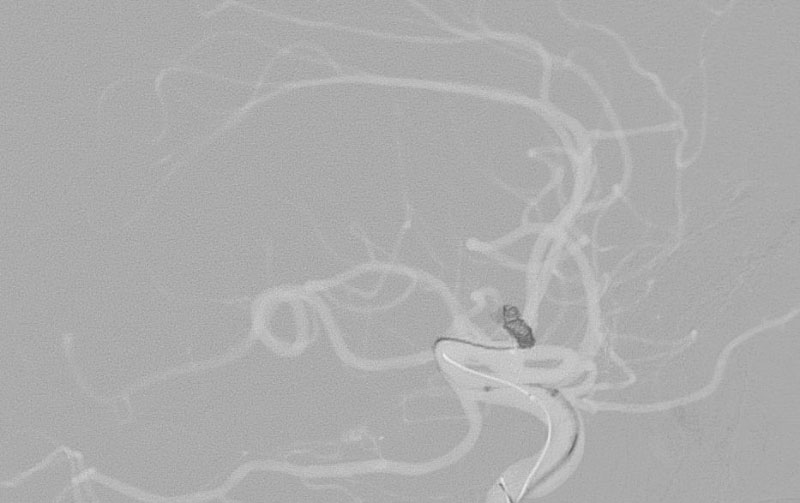

No.1627 手術後